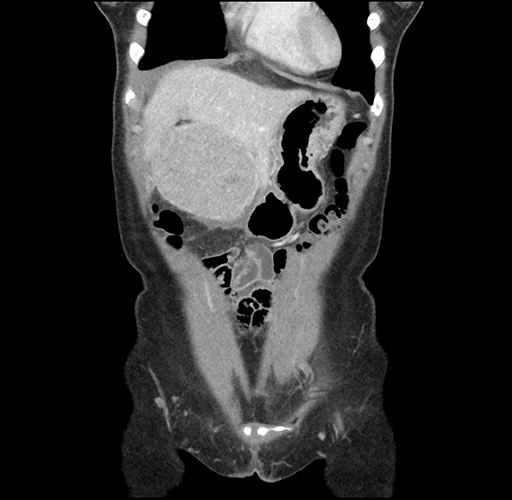

Left lateral sectionectomy [case 12]

Imaging Analysis

Look through the patient's CT scan to identify any areas of concern for the necessary procedure.

Based on your CT findings, which issue(s) would give reason for "planned slowing down moment(s)" in this case?

Considering a standard left lateral sectionectomy procedure, what step(s) of the operation would you do differently in this case ?